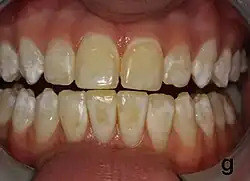

| Mild fluorosis: in its usual mildest form, fluorosis appears as opaque white patches on the enamel | |

Dental fluorosis appears as a range of visual changes in enamel[4] causing degrees of intrinsic tooth discoloration, and, in some cases, physical damage to the teeth. The severity of the condition is dependent on the dose, duration, and age of the individual during the exposure.[1] The "very mild" (and most common) form of fluorosis, is characterized by small, opaque, "paper white" areas scattered irregularly over the tooth, covering less than 25% of the tooth surface. In the "mild" form of the disease, these mottled patches can involve up to half of the surface area of the teeth. When fluorosis is moderate, all of the surfaces of the teeth are mottled and teeth may be ground down and brown stains frequently "disfigure" the teeth. Severe fluorosis is characterized by brown discoloration and discrete or confluent pitting; brown stains are widespread and teeth often present a corroded-looking appearance.[1]